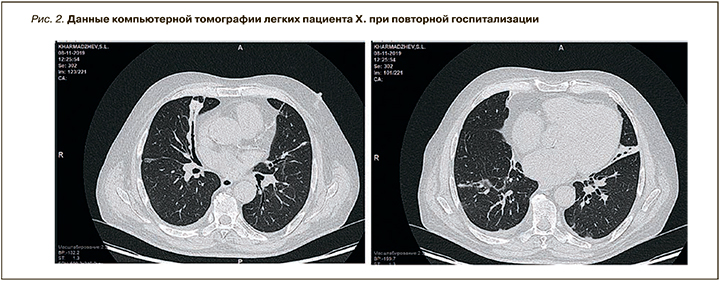

Однако сразу же после выписки из стационара у пациента Х. появился жидкий стул. Врачом поликлиники мужчине была отменена гормональная терапия и назначены препараты Роцефин и Имодиум. В связи с нарастанием боли в животе пациент Х. был повторно госпитализирован в клинику АО «Медицина» 25.10.2019. Состояние его при поступлении было тяжелым, обусловленным дисфункцией желудочно-кишечного тракта и нестабильной гемодинамикой. Температура тела 37,6 °С. В сознании, адекватен, доступен контакту. Склеры желтоватые. Видимые слизистые оболочки розовые, чистые, влажные. Частота дыхания 22–25 в 1 мин. Отмечалась небольшая работа вспомогательной мускулатуры при дыхании. Аускультативно дыхание проводилось во все отделы, ослаблено, больше в заднебазальных отделах. Справа в заднебазальных отделах выслушивались разнокалиберные влажные хрипы, минимальная бронхообструкция. Сатурация составляла 98% при дыхании атмосферным воздухом. Живот был вздут выше реберных дуг, при пальпации мягкий, умеренно болезненный во всех отделах. Аускультативно выслушивалась вялая перистальтика. Частота стула составляла 2–3 раза в день, сам стул был жидким в виде плевков коричневого цвета. Мочился пациент самостоятельно. По данным КТ-исследования легких данных в пользу их поражения выявлено не было (рис. 2).